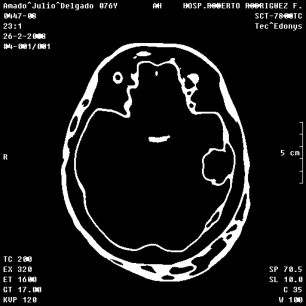

An example of an applications of our proposed strategy to a medical image is shown in Figure 7. In this case, we used different values of and in the . This is a preliminary result. A deeper paper about these results will be published.